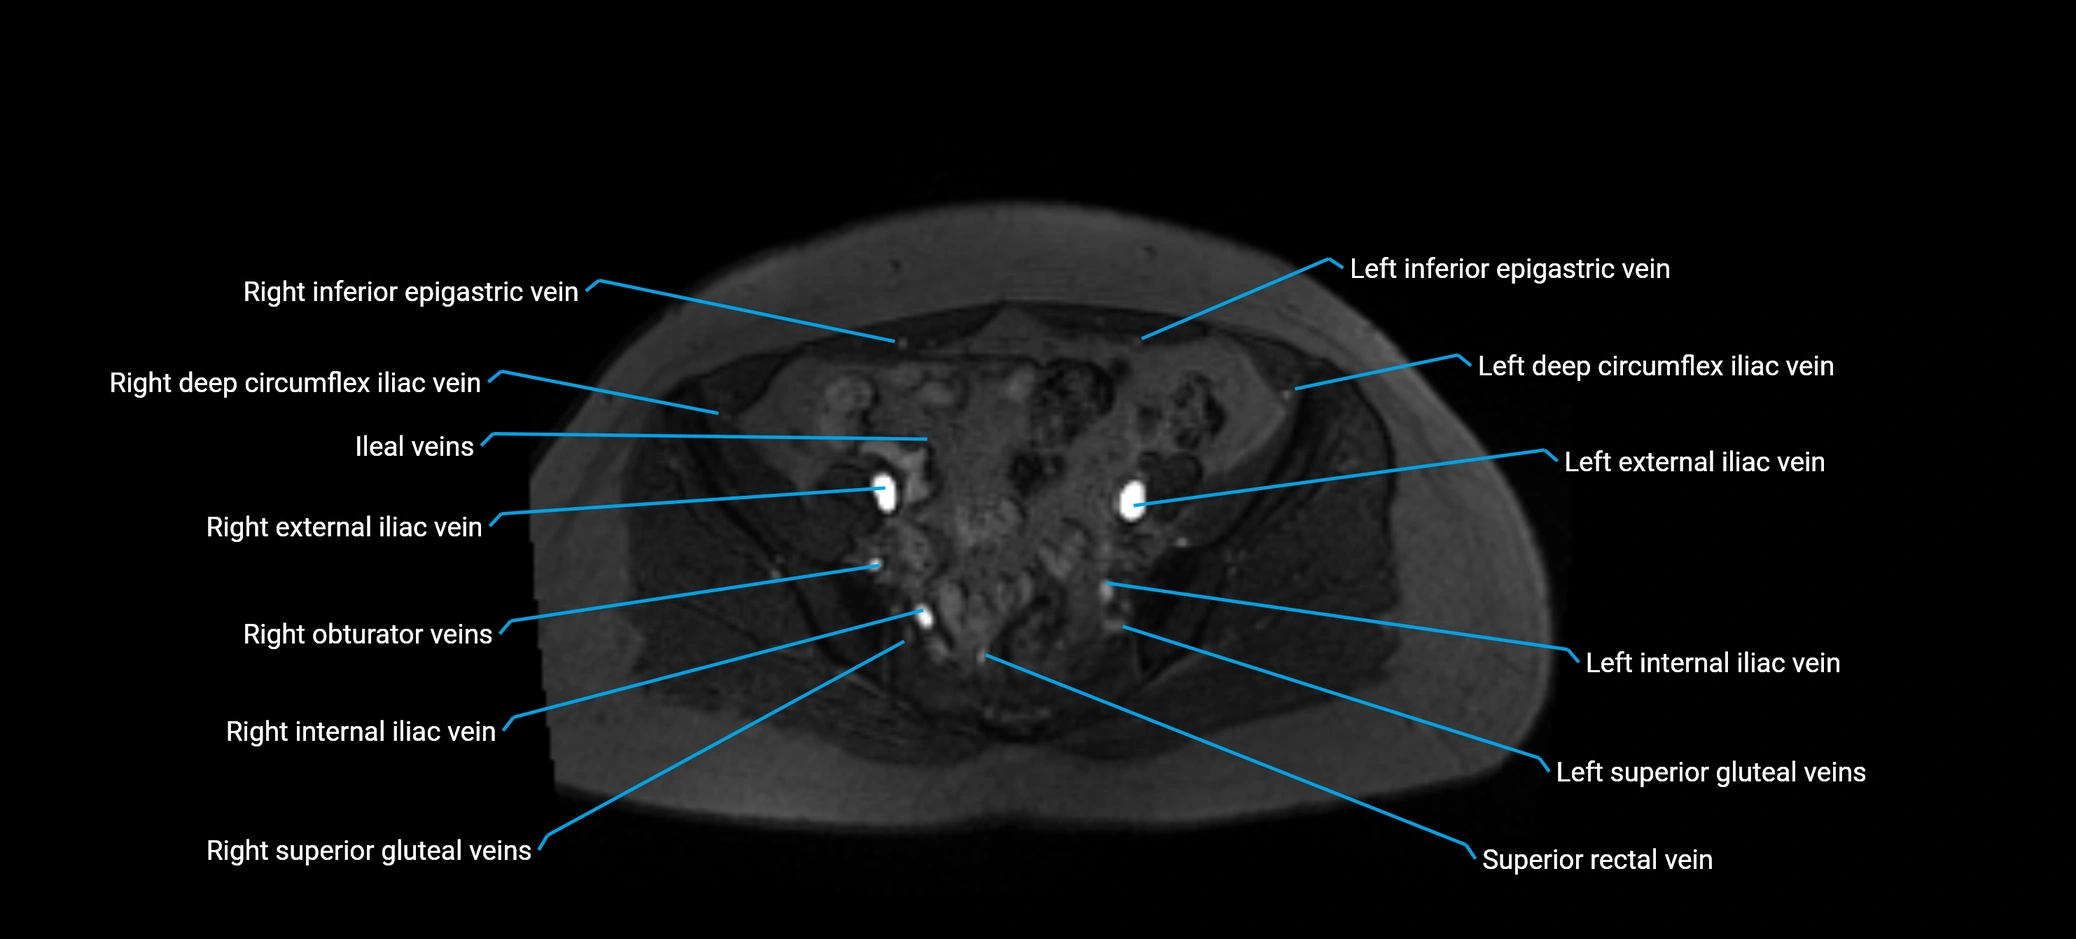

MRI image

image